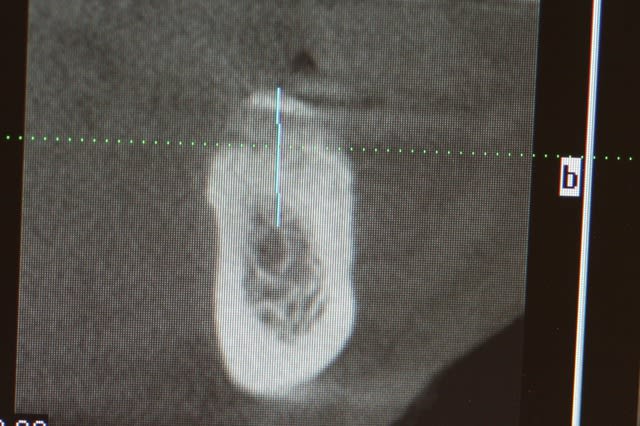

image 11: tomo à 4 mois